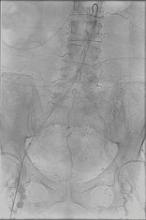

With a patient on the table, an interventional radiologist follows the movement of his catheter through a maze of arterial vessels. As he weaves his catheter through an intricate web of arteries to reach the coronary arteries and the area of interest, he gets constant real-time feedback from the monitors so he can carefully position the catheter to perform the intervention.